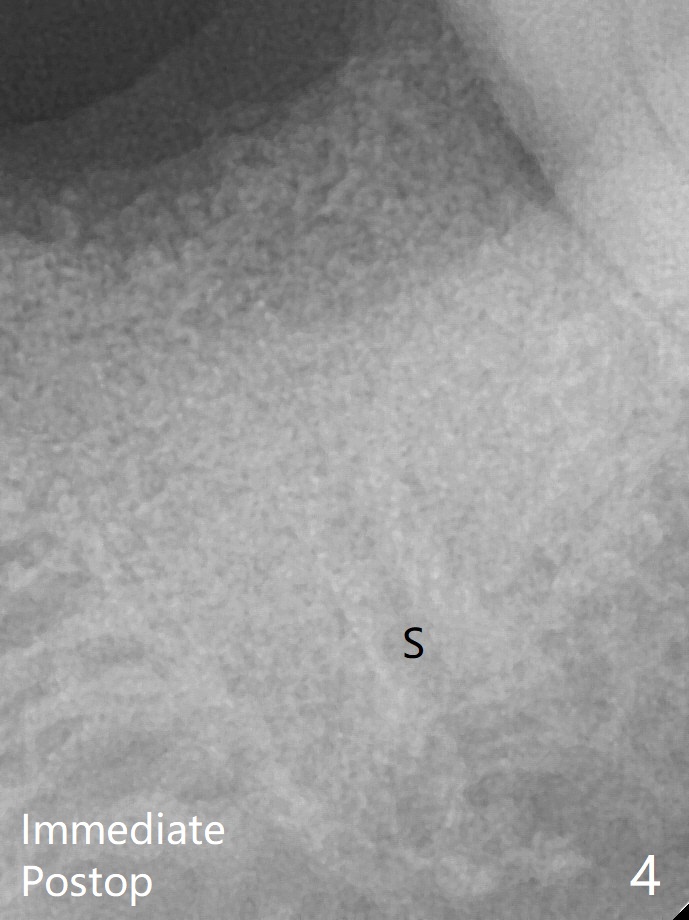

术后三个月牙槽嵴宽(图六);高度稍微减低(图七)。